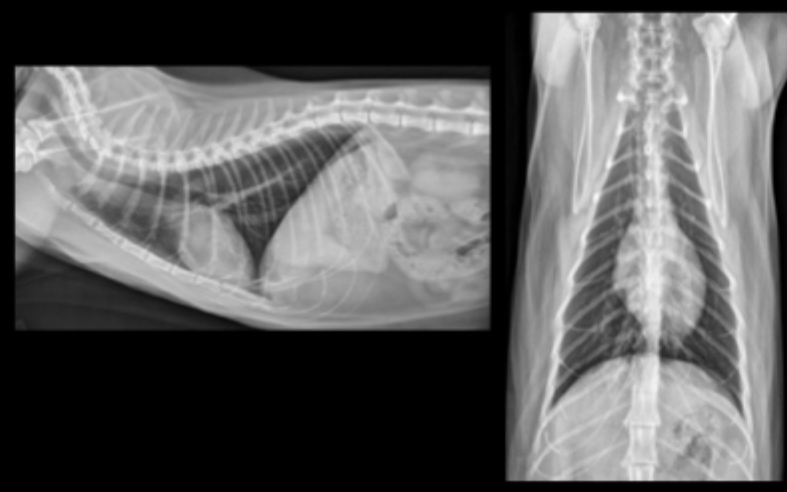

What can be seen on these feline radiographs?

left atrial enlargement

What pulmonary pattern can be seen in this radiograph?

diffuse interstitial pattern

What pattern does feline cardiogenic edema generally present as?

random

patchy

peri-vascular in distribution

True or false: Feline cardiogenic edema will show a dramatic (rapid) response to treatment.

True